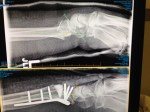

2017: This happened and my world ground to a halt

- Temporary cast before. After surgery.

- Molded wrist brace.